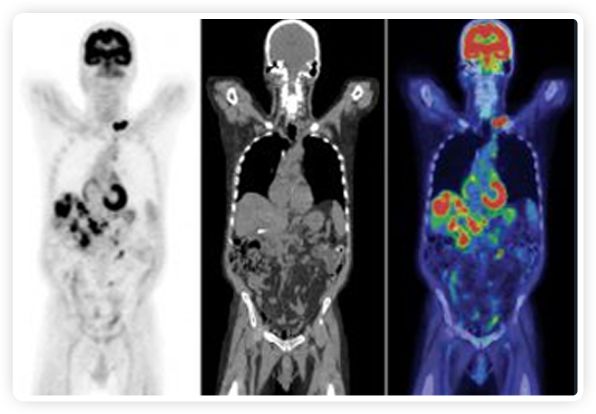

正電子發(fā)射斷層掃描(PET)是癌癥檢測中已建立的成像標準,與其他成像方式相比,PET能提供高靈敏度和特異性的圖像。

到目前為止,放射腫瘤學中(使用的圖像主要是結(jié)構性的,而PET圖像可以提供生物學信息。通過使用注射示蹤劑,例如18-FDG,PET可以描繪腫瘤的代謝活性,使其“點亮”。(FDG是用于可視化癌癥代謝的最廣泛使用的示蹤劑。與正常組織相比,腫瘤細胞保留更高水平的FDG。)不同的PET示蹤劑可以識別腫瘤的不同生物學特征,例如特定生物標志物抗原(例如,PSMA)或甚至探測免疫系統(tǒng)本身(例如,PDL1表達或活化的T細胞)。